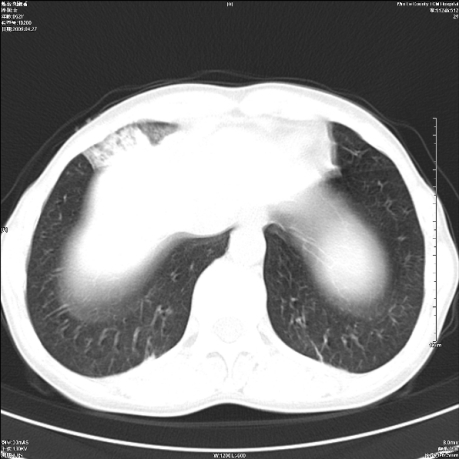

标题: CT19625:女52间断性喀血 [打印本页]

标题: CT19625:女52间断性喀血

考虑右肺中叶感染性病变并右肺中、下叶肺泡积血;建议抗炎、止血治疗后复查。

右肺中叶炎症;右肺中、下叶肺泡积血

右肺中叶支气管扩张并感染或咳血沉积,块右肺中下叶肺泡积血。

右肺中叶慢性炎症伴局部支扩并中下叶肺泡积血。

考虑右肺中叶感染性病变并右肺中、下叶肺泡积血。建议治疗后复查。